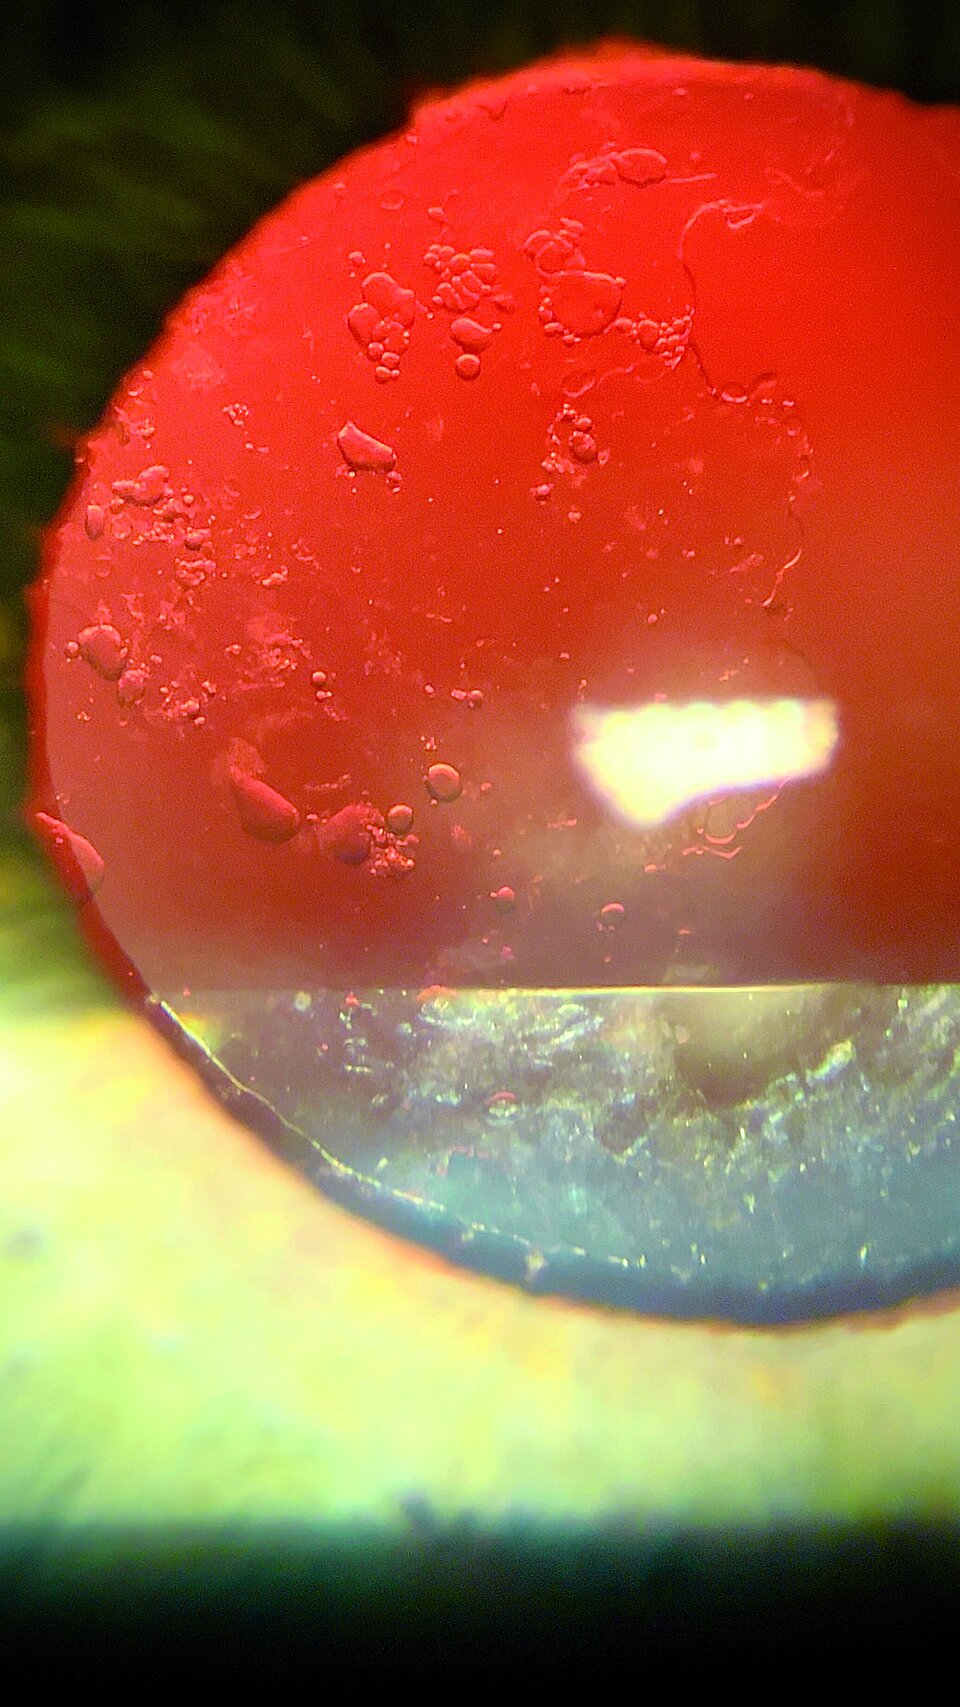

In der augenärztlichen Ambulanz, in der sich der Rentner mit seinem Problem vorstellt, erscheinen beide Augen äußerlich unauffällig. Der Fernvisus beträgt rechts 1.0, links mit Mühe 0.7. Eine Katarakt sollte ausgeschlossen sein, da der Patient bereits drei Jahre zuvor wegen eines fortgeschrittenen Altersstars beidseits eine Kunstlinse implantiert bekommen hatte. Doch in der Spaltlampenuntersuchung zeigen sich im regredienten Licht kleinblasige Eintrübungen an der Hinterkapsel des linken Auges, die wohl die Visusverschlechterung verursachen. Bei direkter Beleuchtung entpuppen sie sich als großflächige Trübung.

Kleinblasige Eintrübungen in der Hinter­kapsel führten in diesem Fall zu einer großflächigen Visusminderung. Kleinblasige Eintrübungen in der Hinter­kapsel führten in diesem Fall zu einer großflächigen Visusminderung. © Eyepress Fachmedien GmbH, Mülheim a. d. Ruhr